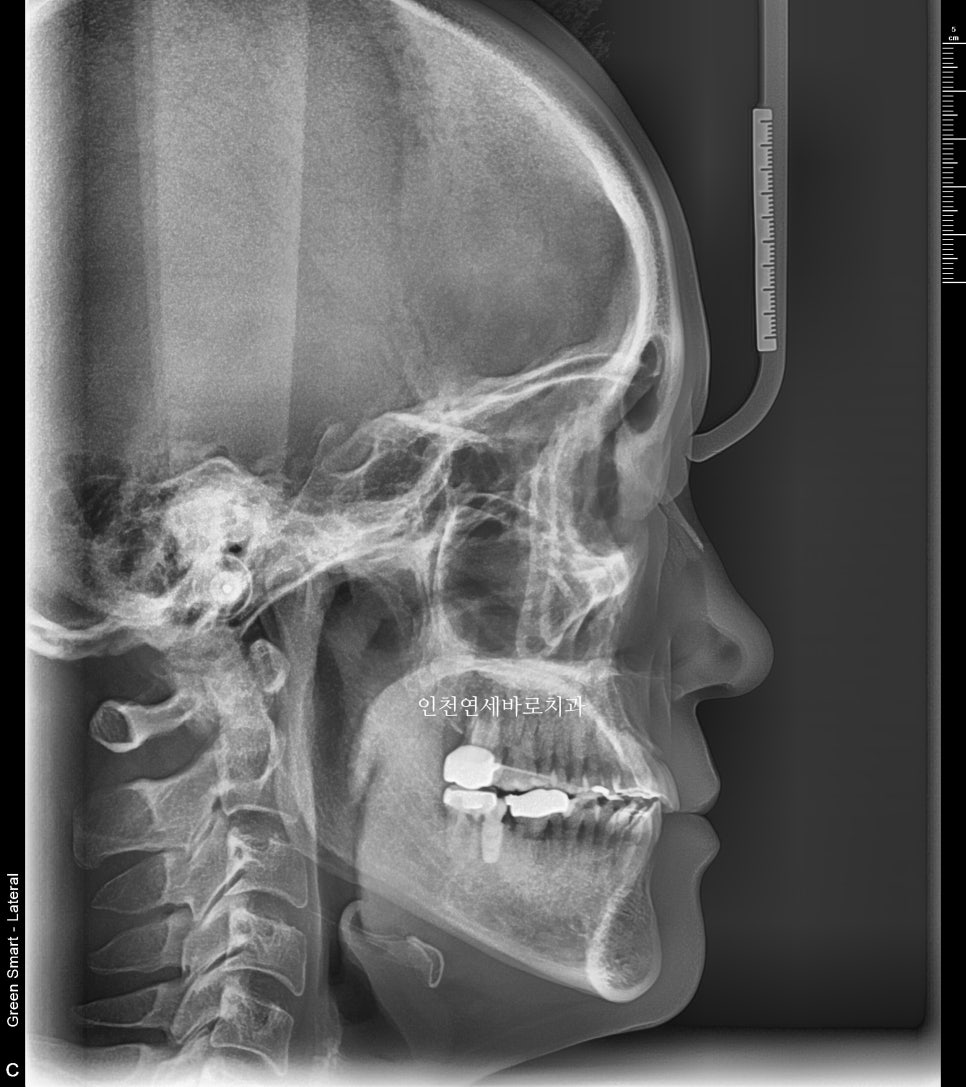

전후 엑스레이입니다

양악수술은 아니기에 큰 변화는 아니지만 안모의 개선을 확인 가능할겁니다.